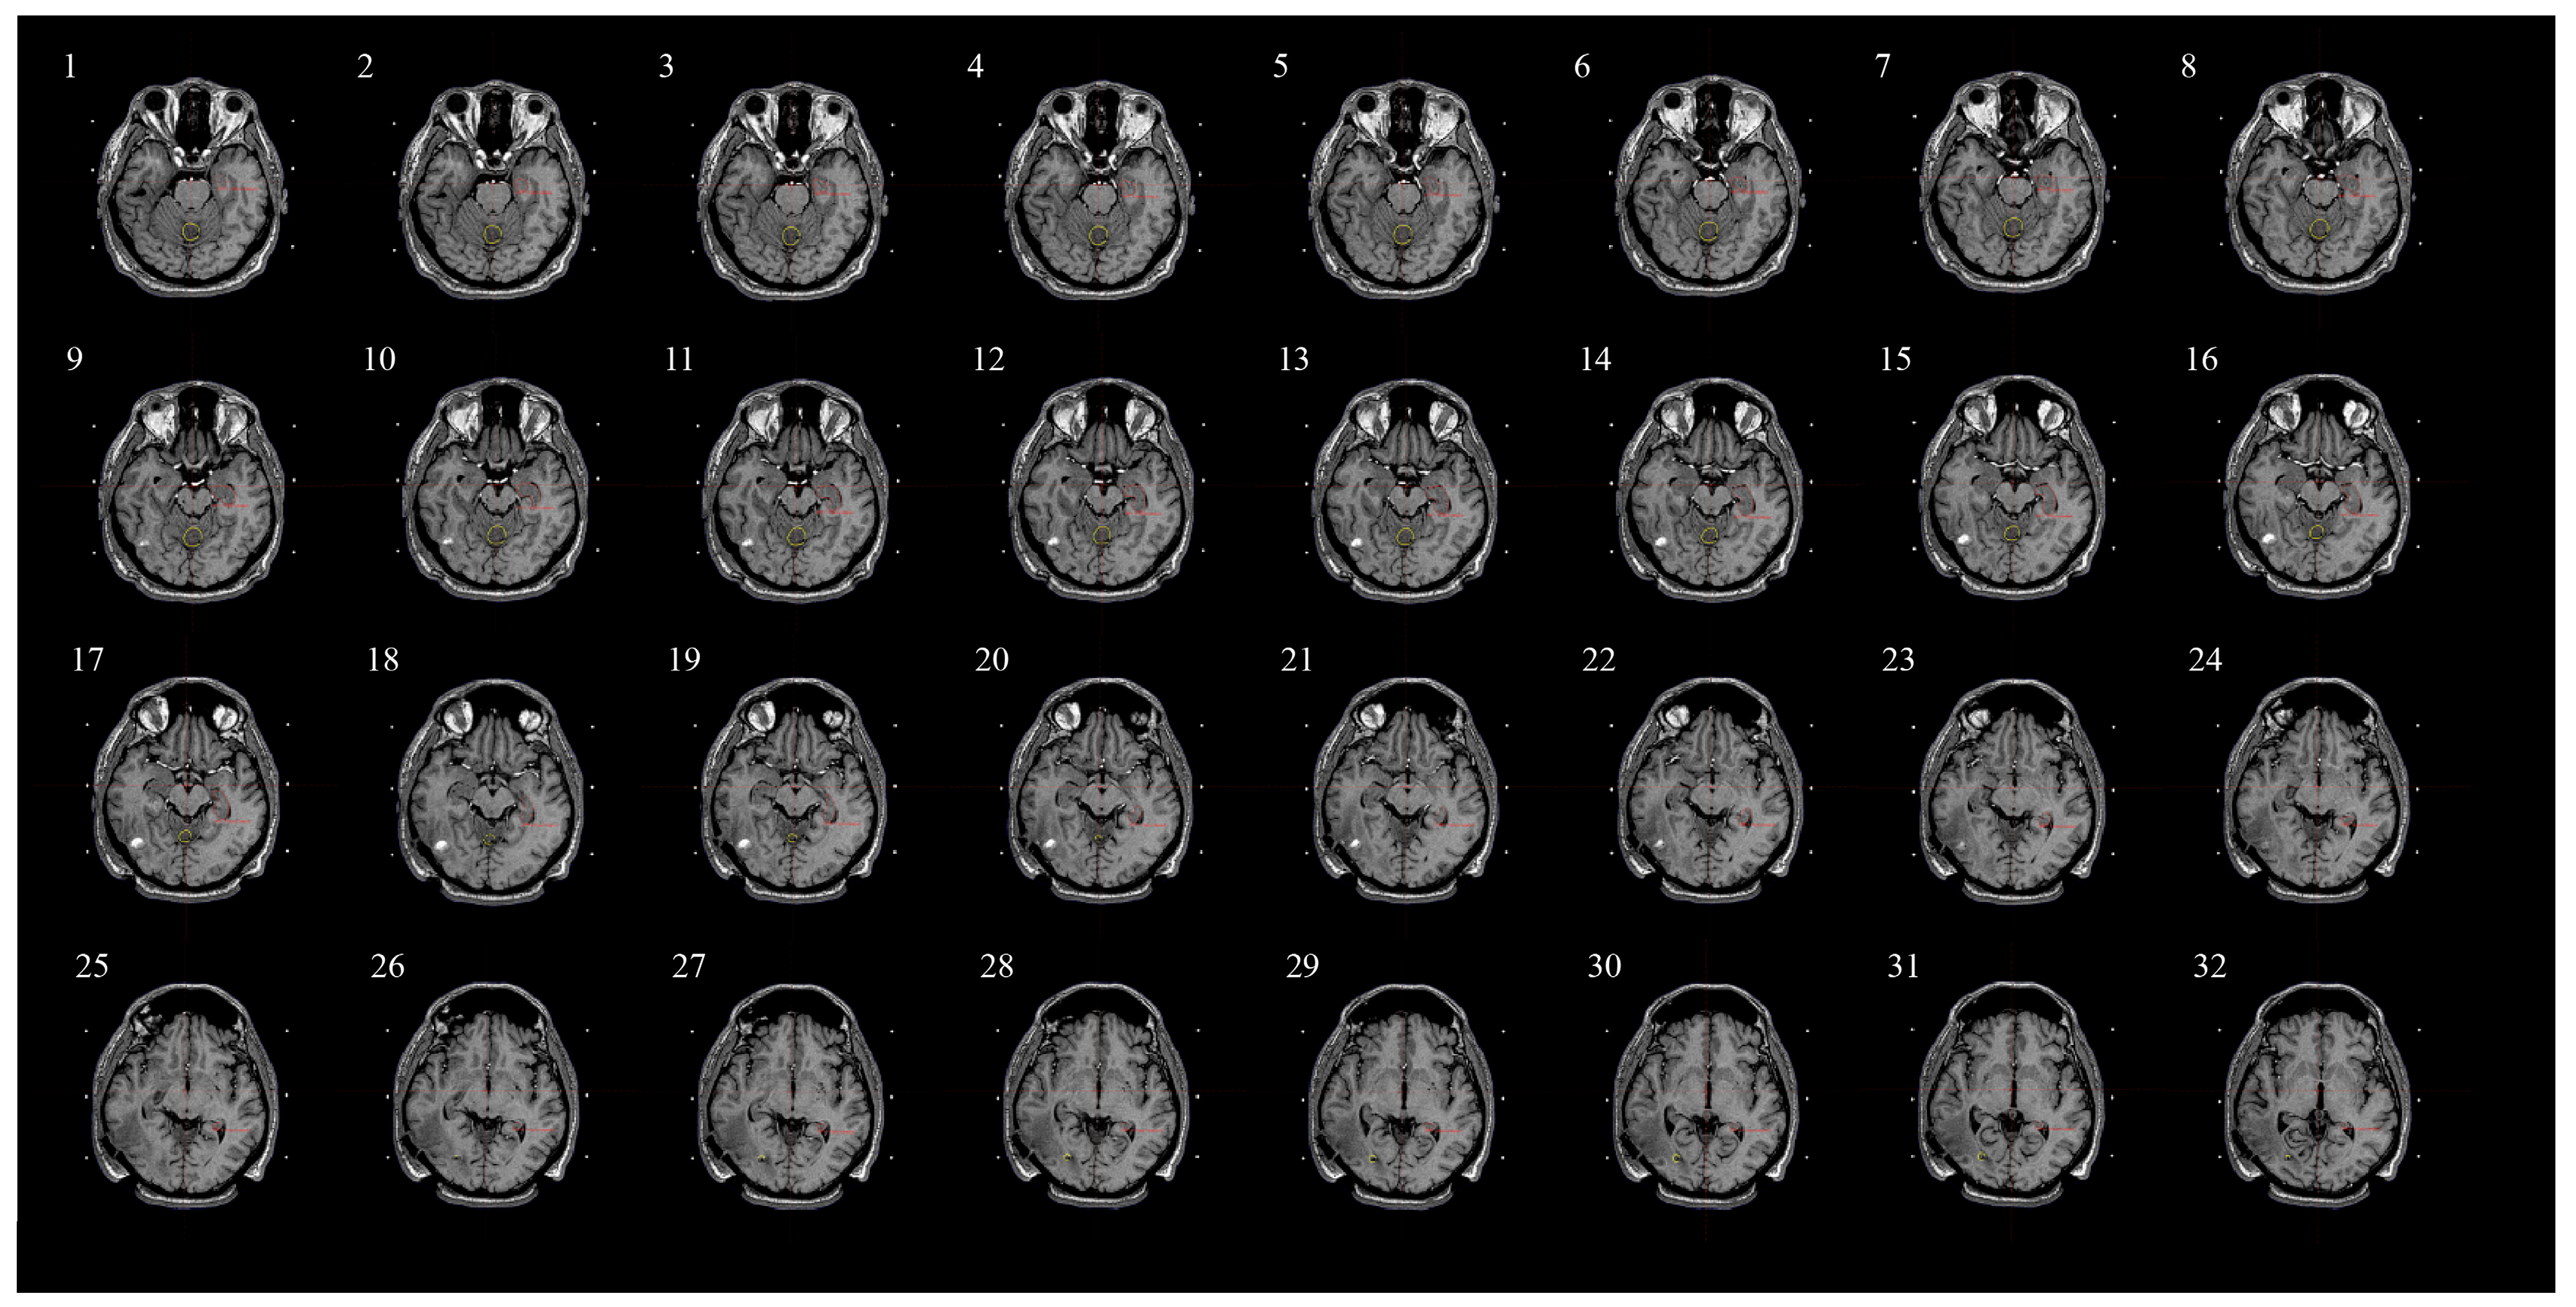

2.5. Assessing Radiation Dose to Hippocampi and Contouring Process